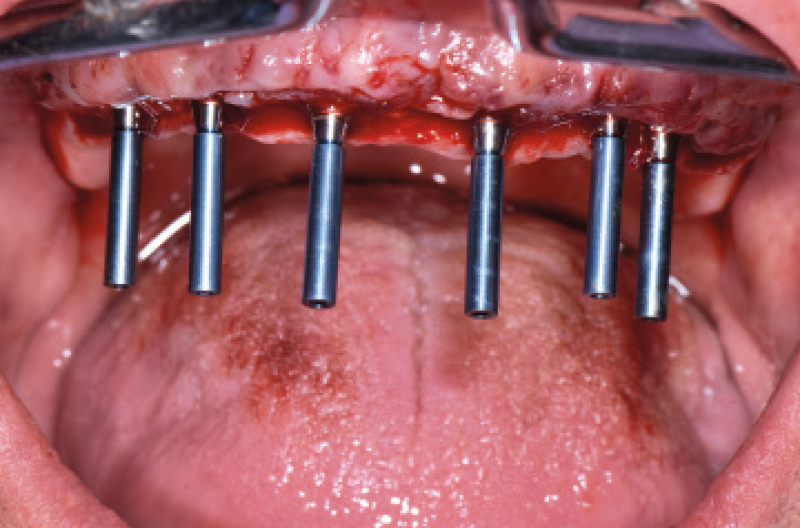

Nel mese di luglio 2019 il paziente ├© stato operato con il contestuale inserimento di 10 impianti, 4 nellŌĆÖarcata inferiore e 6 nellŌĆÖarcata superiore. Ho inserito 4 impianti Max Stability ├ś 3,75 mm nella zona della premaxilla, uno lungo 10 mm e gli altri tre da 12 mm di lunghezza; in regione 15 e 25 ho dovuto invece utilizzare delle frese da osseodensificazione per compattare lŌĆÖosso e traslare la parete mediale del seno mascellare per poter inserire 2 impianti Max Stability ├ś 3,75 L 12 mm inclinandoli lungo la parete stessa. Data la scarsa quantit├Ā e qualit├Ā di osso nel mascellare, ho rinunciato al carico immediato rinviando la procedura della protesizzazione immediata nella fase di riapertura degli impianti ad osteointegrazione avvenuta (Figg. 1-14).

Fig. 8 – Impianti frontali inseriti

Fig. 9 – Osseodensificazione e traslazione parete mediale del seno mascellare di destra

Fig. 10 – Impianto in regione 15 inclinato lungo la parete mediale del seno

Fig. 11 – Osseodensificazione e traslazione parete mediale del seno mascellare di sinistra

Fig. 12 – Posizionamento dei tappi di chiusura